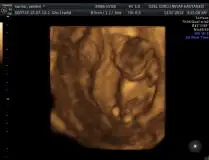

Hiçbirşey görünmüyor ki kız göbek kordunu görünüyor bacakta kapalı zaten kaç boyutlu ola bu ultrason bizimkinin eski makinesi

sadece bu yok canım belki yarım saat incelendi ikili test yapıldı. hem iki boyutlu hem 3 boyutlu baktı. evet benim doktorun makinası güzel prof ondan heralde